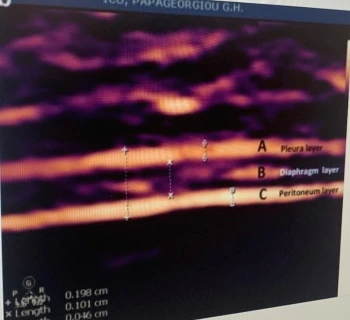

다음으로 교수님이 초음파로 Diaphragm을 보는 모습을 보았다. 오른쪽에서는 간을, 왼쪽에서는 신장을 찾으며 가이드로 찾아가는데 처음으로 초음파로 diaphragm을 봐서 신기할 따름이었다. 궁금해하니 교수님이 아래와 같은 강의록을 보여주며 조금 더 설명해주셨다.

강의록에 나와있던 초음파 사진, 3개의 층.